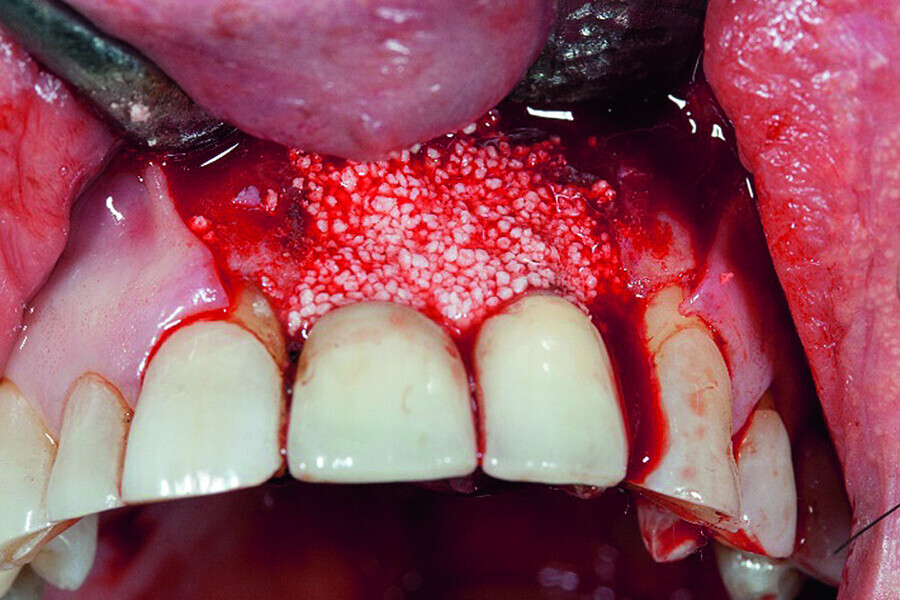

Peri-implantitis therapy